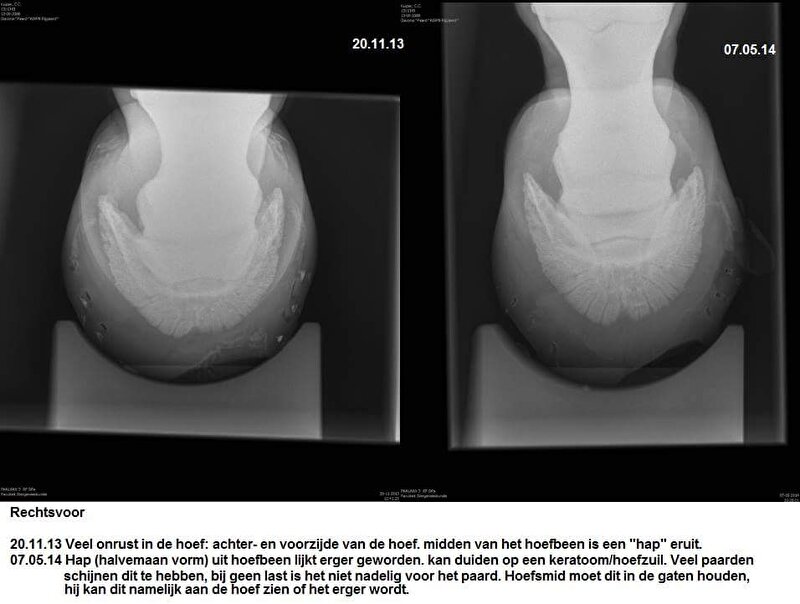

Hier nog wel wat foto's van haar herstel:

Cardy @ [BEH] White Line Disease.. al 12 weken uit de running. Ervaring?